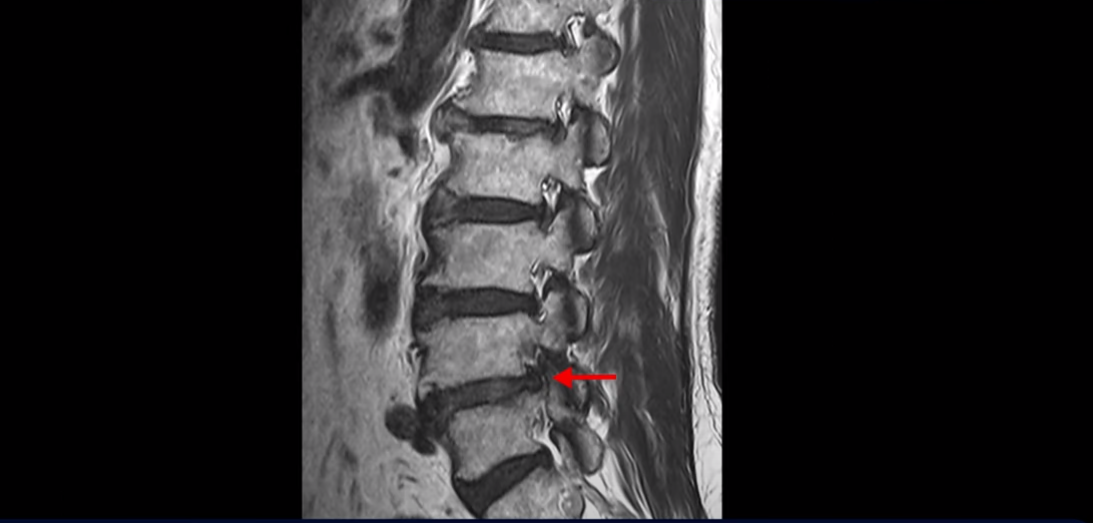

이분 MRI를 보면 척추의 여러 마디가 퇴행이 진행되어 안 좋습니다.

특히 4번 5번 마디가 제일 안 좋은데 보시다시피, 하얗게 보여야 될 신경이 거의 안 보일 정도로 척추관이 좁아져 있습니다.

이분은 다리가 너무 아파 걷기 어려워 지팡이를 짚고 모커리에 내원하셨는데요. 어떻게 이런 환자분들을 수술 없이 치료해서 잘 걷게 만들고 심지어는 지팡이 없이 걷게 만들 수 있을까요? 또 어떻게 굽어진 허리가 펴질까요? 지금부터 설명해드립니다.